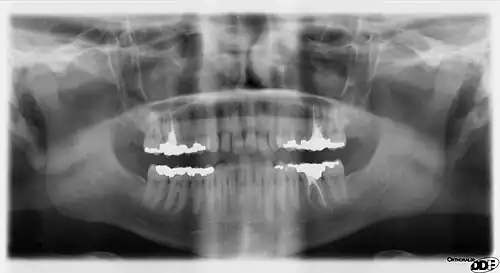

Dental radiographs, commonly known as X-rays, are radiographs used to diagnose hidden dental structures, malignant or benign masses, bone loss, and cavities.

A radiographic image is formed by a controlled burst of X-ray radiation which penetrates oral structures at different levels, depending on varying anatomical densities, before striking the film or sensor. Teeth appear lighter because less radiation penetrates them to reach the film. Dental caries, infections and other changes in the bone density, and the periodontal ligament, appear darker because X-rays readily penetrate these less dense structures. Dental restorations (fillings, crowns) may appear lighter or darker, depending on the density of the material.

It is possible for both tooth decay and periodontal disease to be missed during a clinical exam, and radiographic evaluation of the dental and periodontal tissues is a critical segment of the comprehensive oral examination. The photographic montage at right depicts a situation in which extensive decay had been overlooked by a number of dentists prior to radiographic evaluation.

Panoramic films

Panoramic films are extraoral films, in which the film is exposed while outside the patient's mouth, and they were developed by the United States Army as a quick way to get an overall view of a soldier's oral health. Exposing eighteen films per soldier was very time consuming, and it was felt that a single panoramic film could speed up the process of examining and assessing the dental health of the soldiers; as soldiers with toothache were incapacitated from duty. It was later discovered that while panoramic films can prove very useful in detecting and localizing mandibular fractures and other pathologic entities of the mandible, they were not very good at assessing periodontal bone loss or tooth decay.[18]